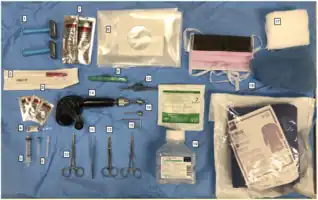

Equipment needed for a cranial burr hole.[1]

Equipment needed for a cranial burr hole.[1]